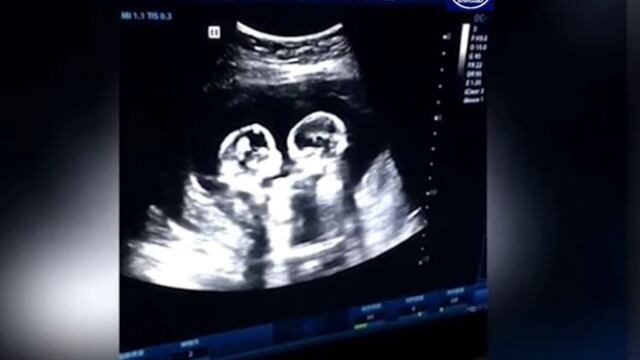

Así, un hombre chino de 28 años identificado como Tao, captó en video el gracioso momento en que sus dos pequeñas hijas parecen luchar por el espacio que ocupaban dentro del útero de su madre, todo revelado por una ecografía.

Obviamente las hijas de Tao que en aquel momento tenían sólo cuatro meses, no peleaban pero sus movimientos hacen que parezca al menos un enfrentamiento entre el Canelo Álvarez y Manny Pacquiao.

Tao declaró a los medios locales, que esta no fue la única vez que vio a sus hijas hacer algo hermoso aún estando en el vientre de la madre; que unas semanas antes, durante otra ecografía, las encontraron abrazadas.